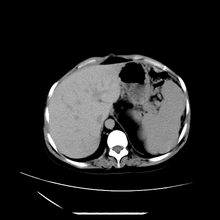

女性,41岁,发现左腹部包块3年,现行ct检查,检查前做过静脉肾盂造影。

左侧低密度区是脂肪密度,中间可见条索状软组织样密度影,现主要想知道左肾前下缘圆形软组织样密度影,内见低密度水样密度影,这是什么?

脾脏增大,左肾后方脂肪增多,脊柱前方脂肪增多,左肾窦脂肪增多,左肾变形,双肾积水以左侧为著,左肾内侧及上方见环形软组织肿物影,内部低密度区,考虑1盆腹腔/腹膜后及左肾窦脂肪增多症2左肾内侧病灶可能为左肾上腺病灶,可能为脂肪增多的原凶

1)考虑左肾替代性脂肪瘤病;不排除左肾错构瘤。2)双肾积水。

肾窦脂肪瘤病及肾替代性脂肪瘤病被认为是脂肪增殖程度不同的一种疾病。正常情况下肾窦内有少量脂肪组织充填,在某种情况下肾实质会发生萎缩,而以肾窦、肾门为中心脂肪或(和)纤维组织可出现增殖,当增殖局限在肾窦、肾门区时称为肾窦脂肪瘤,若同时部分或全部取代了萎缩破坏的肾实质时称为肾替代性脂肪瘤病。

发病机理有2种学说,大部分人认为是由于某些具有破坏性的肾脏疾病,如肾结石并感染、肾结核等造成肾破坏、萎缩,继发了大量的脂肪组织增殖;另一部分则认为肾脏慢性炎症可刺激脂肪组织的增殖,肾萎缩是继发的。

ct典型表现为以肾窦肾门为中心大量弥漫性脂肪积聚,鹿角状结石及萎缩的肾实质。合并肾周感染时,肾轮廓不清,周围有粘连性改变。

诊断主要需与含脂肪的肾肿瘤加以区别,如血管平滑肌脂肪瘤、脂肪肉瘤、脂肪瘤